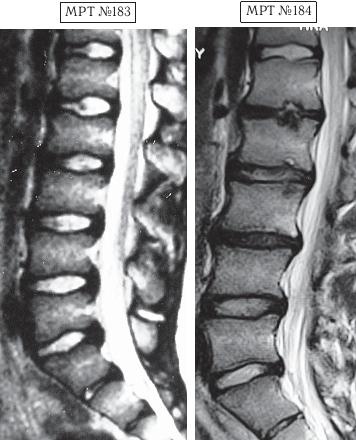

В первом случае у пациента, спустя определённое время, случилось сильное обострение. Сделали МРТ № 179, диагностировали секвестрированную грыжу межпозвонкового диска. Родители первого парня привели его на лечение ко мне в клинику. Так случилось, что в тот же день за консультацией обратились родители второго парня вместе с ним. Они также принесли снимки (МРТ № 183). У второго парня наблюдалась начальная стадия развития остеохондроза. В принципе ничего сложного, можно было подкорректировать, восстановить здоровье и этого юного пациента. Однако случилось так, что родители первого парня, в отличие от родителей второго, остановили свой выбор на клинике вертеброревитологии. Их сын прошёл курсы лечения данным методом и теперь за здоровье парня можно только порадоваться.

На МРТ № 183 наблюдается состояние поясничного отдела позвоночника — начальная стадия развития остеохондроза практически во всех сегментах позвоночника.

На МРТ № 184 того же пациента — состояние поясничного отдела позвоночника после активного укрепления мышц спины физическими упражнениями (кинезитерапии): спондилёз, грыжи Шморля в сегментах ТXII—LI, LI—LII, LII—LIII, практически полное отсутствие межпозвонкового диска в сегменте L–Lu, значительное снижение высоты межпозвонковых дисков в сегментах LII—LIII, LIII—LIV, исправление физиологического лордоза, стеноз спинномозгового канала. Кроме того, помимо всего вышеперечисленного у пациента на уровне поражённых сегментов развился спондилоартроз.